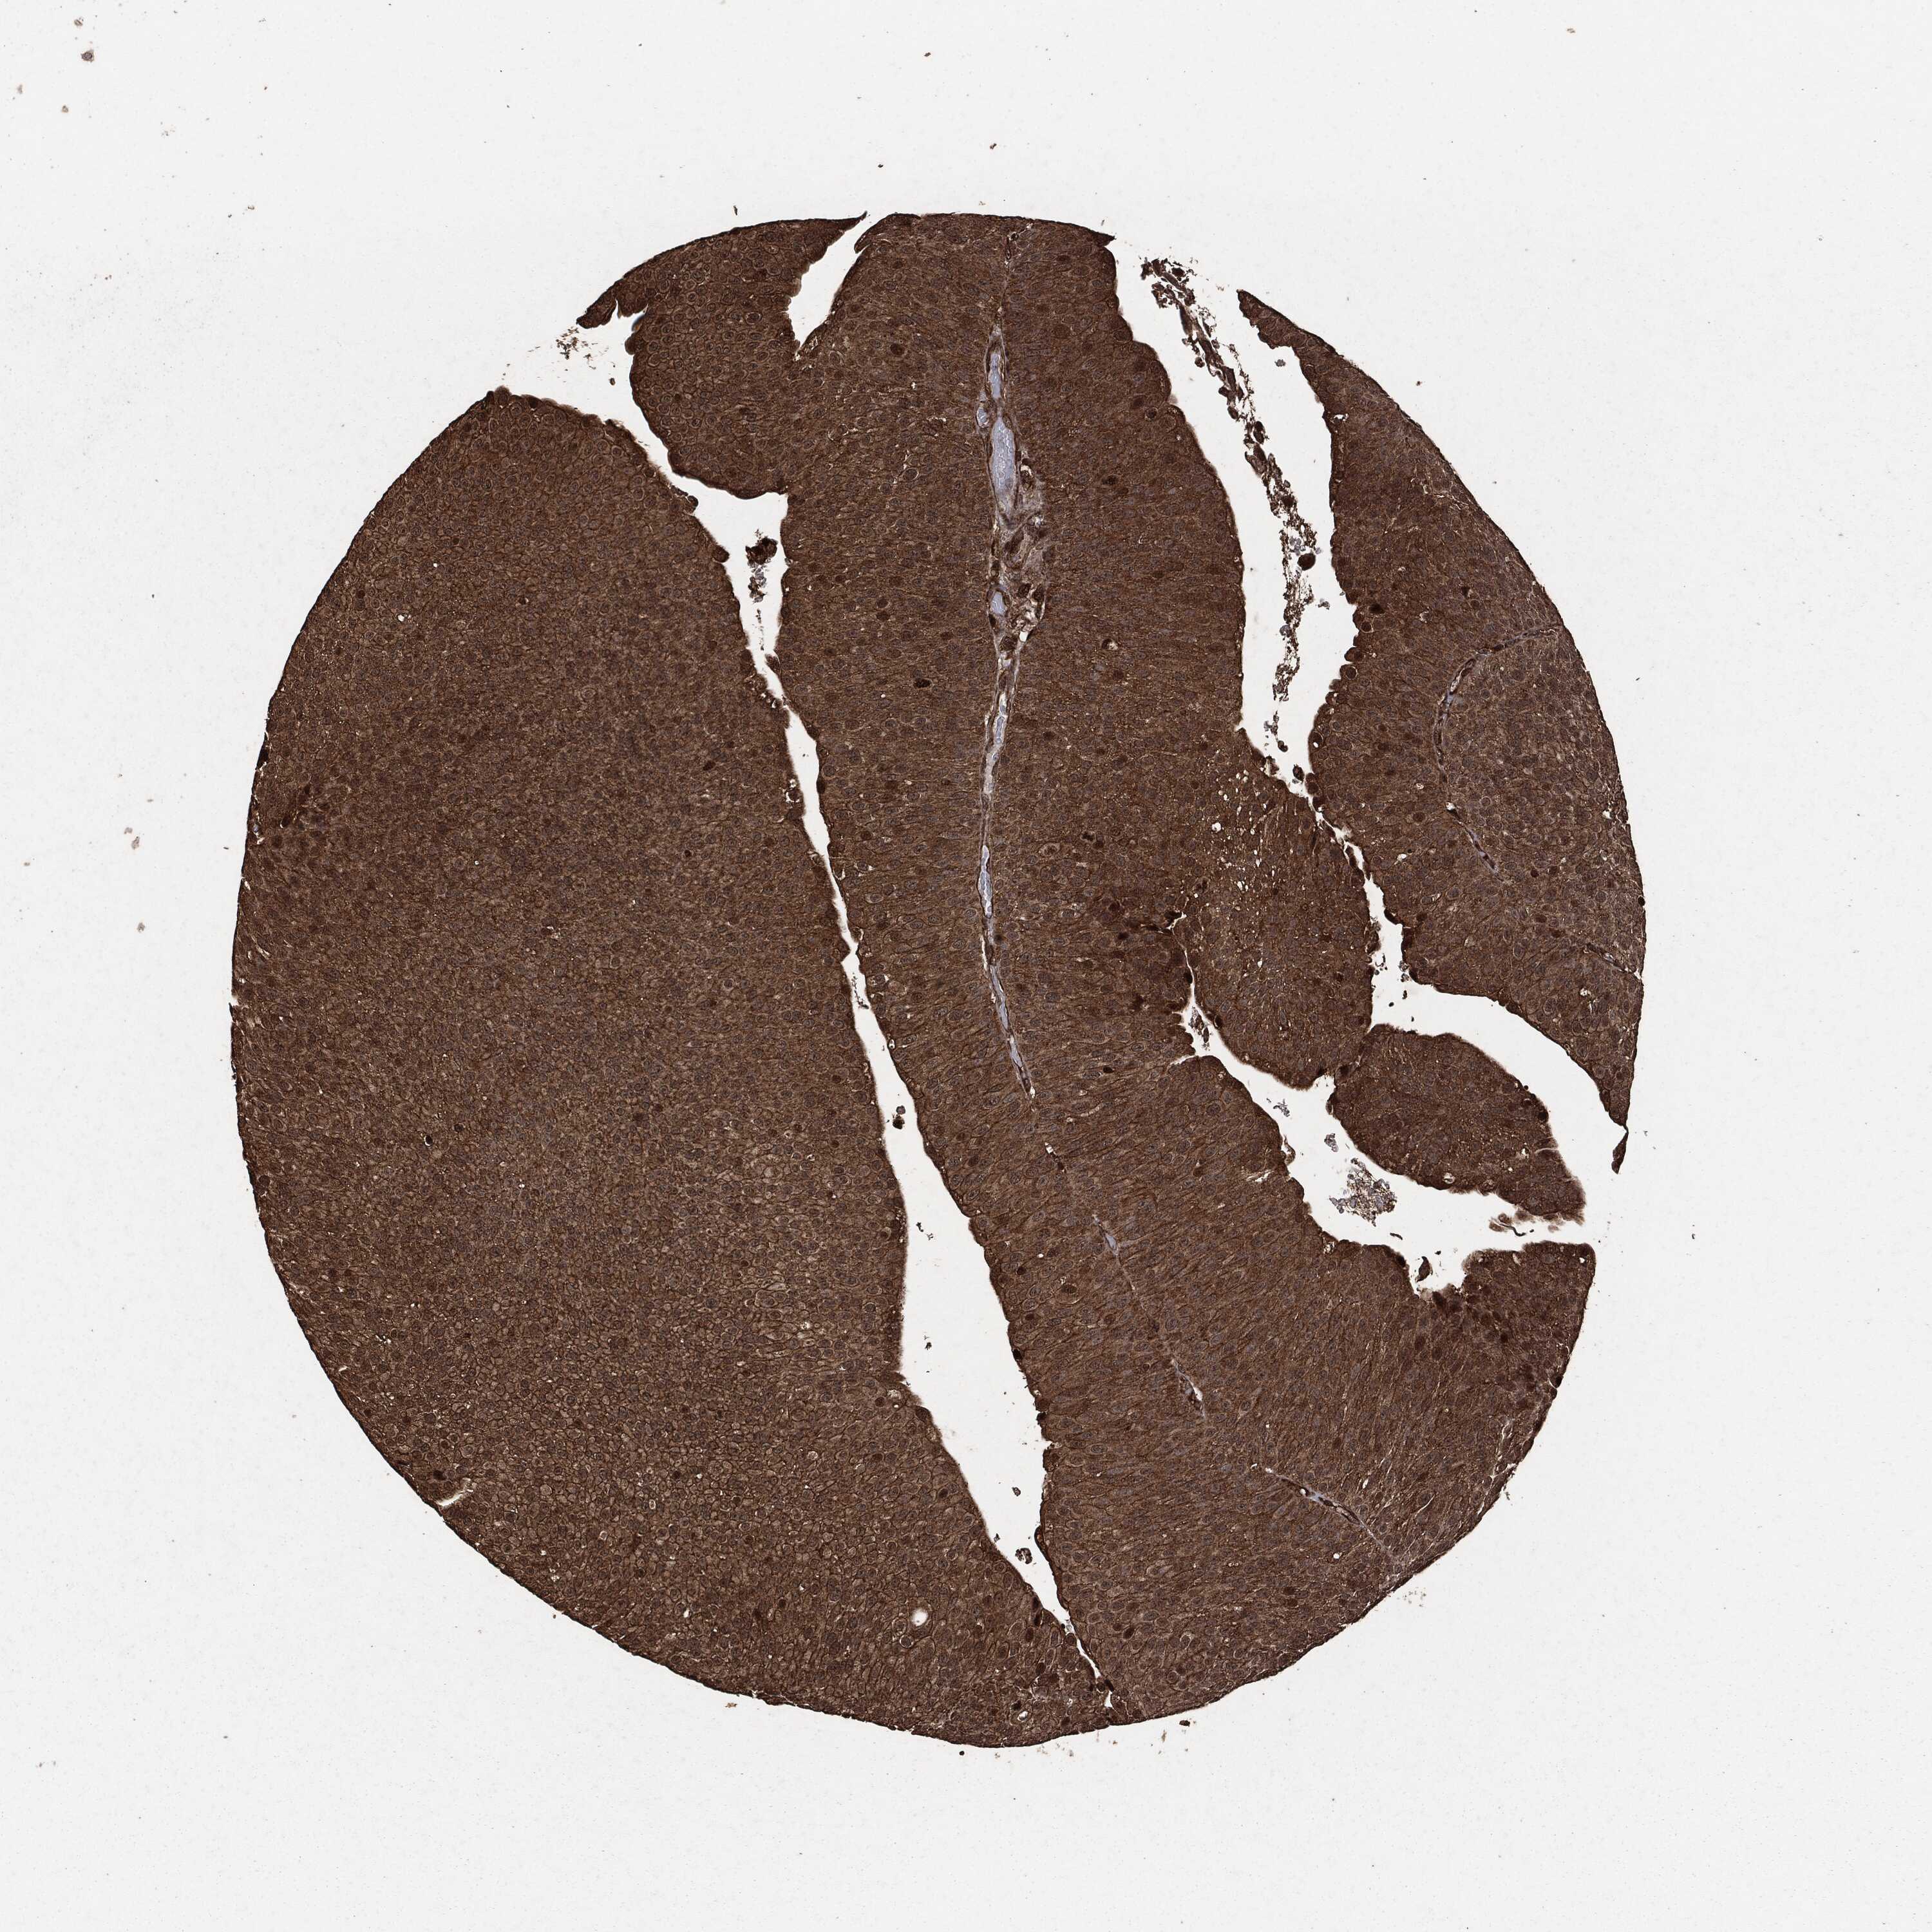

UROTHELIAL CANCER - Protein expressioni

A mouse-over function shows sample information and annotation data. Click on an image to view it in a full screen mode. Samples can be filtered based on level of antibody staining by selecting one or several of the following categories: high, medium, low and not detected. The assay and annotation is described here.

Note that samples used for immunohistochemistry by the Human Protein Atlas do not correspond to samples in the TCGA dataset.

Antibody stainingi

Antibody staining in the annotated cell types in the current human tissue is reported as not detected, low, medium, or high, based on conventional immunohistochemistry profiling in selected tissues. This score is based on the combination of the staining intensity and fraction of stained cells.

Each image is clickable and will lead to virtual microscopy that enables deeper exploration of all samples and also displays staining intensity scores, fraction scores and subcellular localization as well as patient and tissue information for each sample.

HPA049830

CAB002015

CAB080330

CAB080331

CAB080332

Urothelial carcinoma, High grade

Urothelial carcinoma, NOS

Urothelial carcinoma, Low grade

Adenocarcinoma, NOS